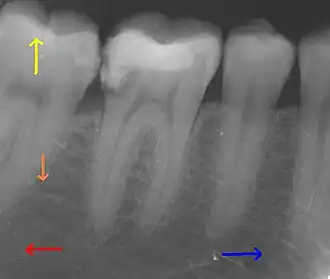

This X-ray film depicts some of the teeth in the lower right quadrant. The arrows point in the following directions: distal ←, mesial →, coronal ↑, apical ↓.